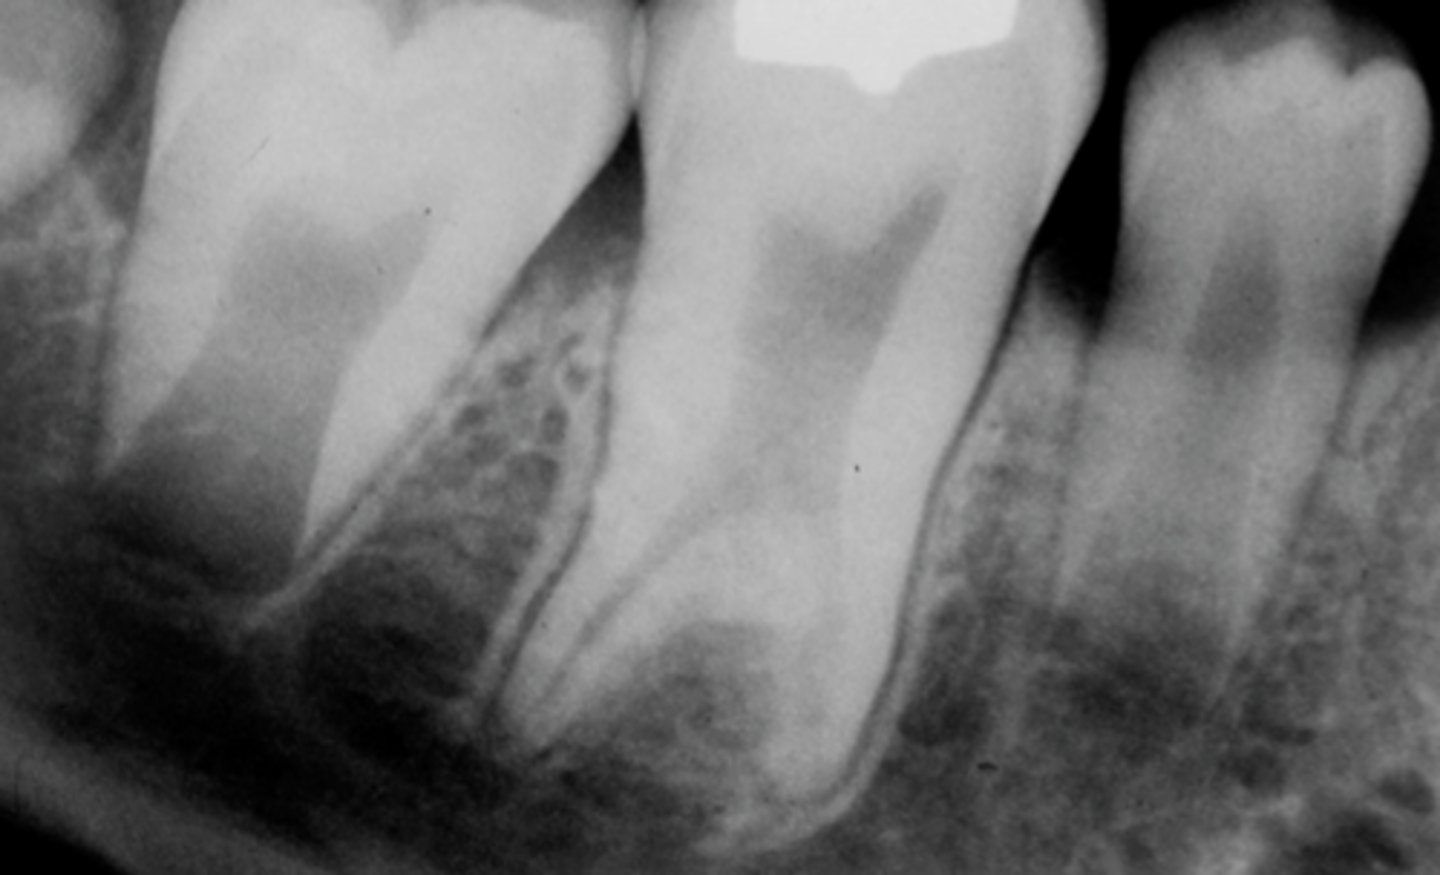

What characterizes asymmetric widening of PDL?

Loss of lamina dura